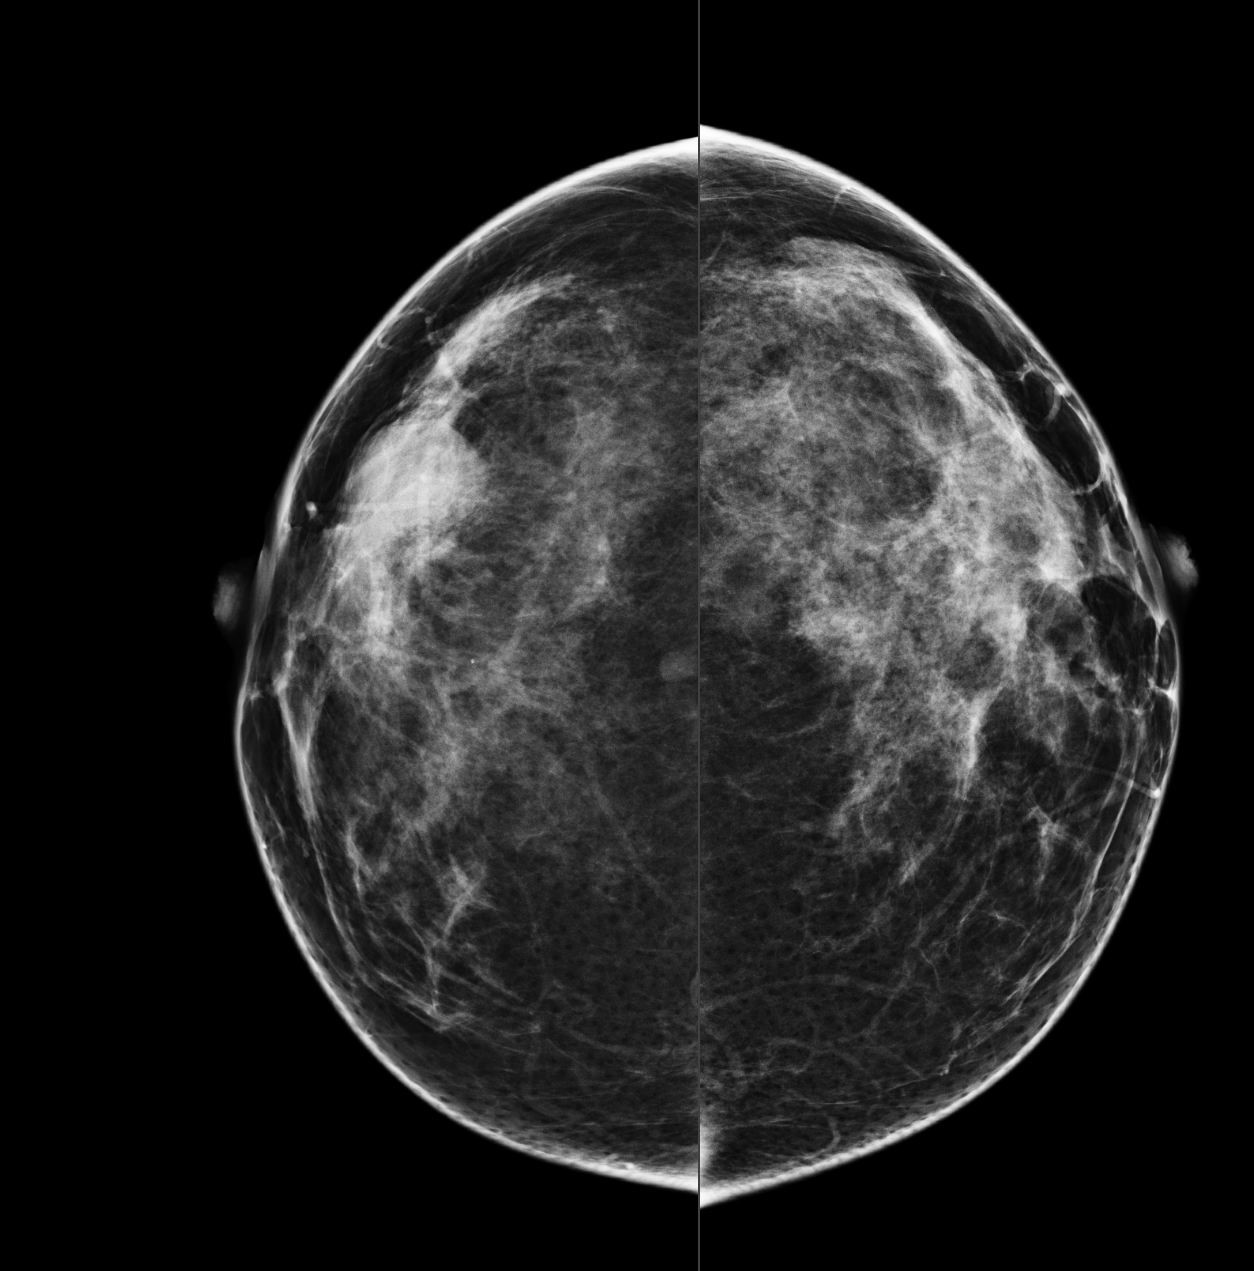

Bilateral Digital mammography , Craniocaudal (CC) and Mediolateral oblique (MLO) view with tomosynthesis images revealed a round shaped, equal density mass with indistinct margin in lower outer quadrant. No suspicious microcalcifications was seen. No significant axillary lymph nodes were present. A high resolution ultrasound of the right breast showed a round shaped, heterogeneously hypoechoic mass with irregular margin, small cystic spaces within and posterior acoustic enhancement, measuring about 1.6x1.9x1.5cm at 7 O’clock position. Mild internal vascularity was noted on colour doppler images. Right axilla showed suspicious lymph nodes with loss of fatty hilum and thickened cortex.